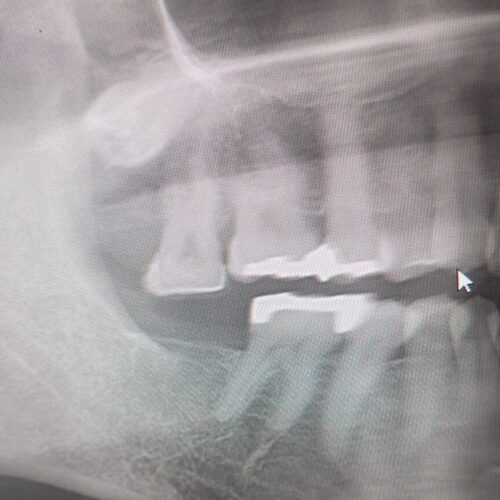

歯を抜いたままにすると 噛み合う相手を失った 写真のレントゲンのように 歯は動きます。

これを戻すには 矯正で 押しこむ方法しかありません。

やっと 下にインプラントの歯のスペースができました

押し込むのに半年以上かかりました。

もう少し押し込みたいので もうしばらく頑張ってもらわないといけません。